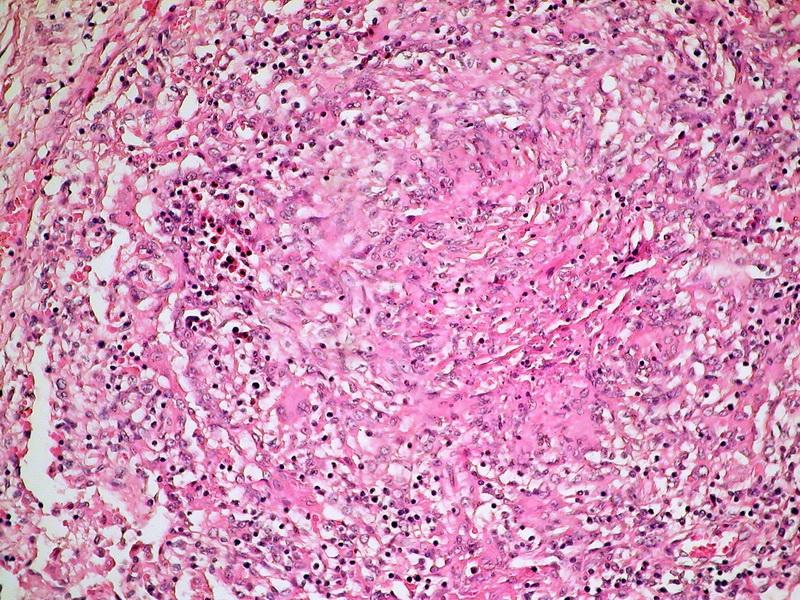

• Plămân cu leziuni de emfizem interstiţial şi alveolar; edem pulmonar şi interstiţial; rare granuloame de tip tuberculoid; sunt prezente focal membrane hialine şi microtrombi trombocitari la nivelul capilarelor pulmonare (fig. 4,5);

• Inima cu rabdomioliză subendocardică, edem interstiţial şi focal. În interstiţiu, colecţie de celule inflamatorii alcătuite din macrofage, rotundonucleare şi eozinofile. În peretele venei jugulare trombozate, infiltrate celulare rotundonucleare, eozinofile şi macrofage;